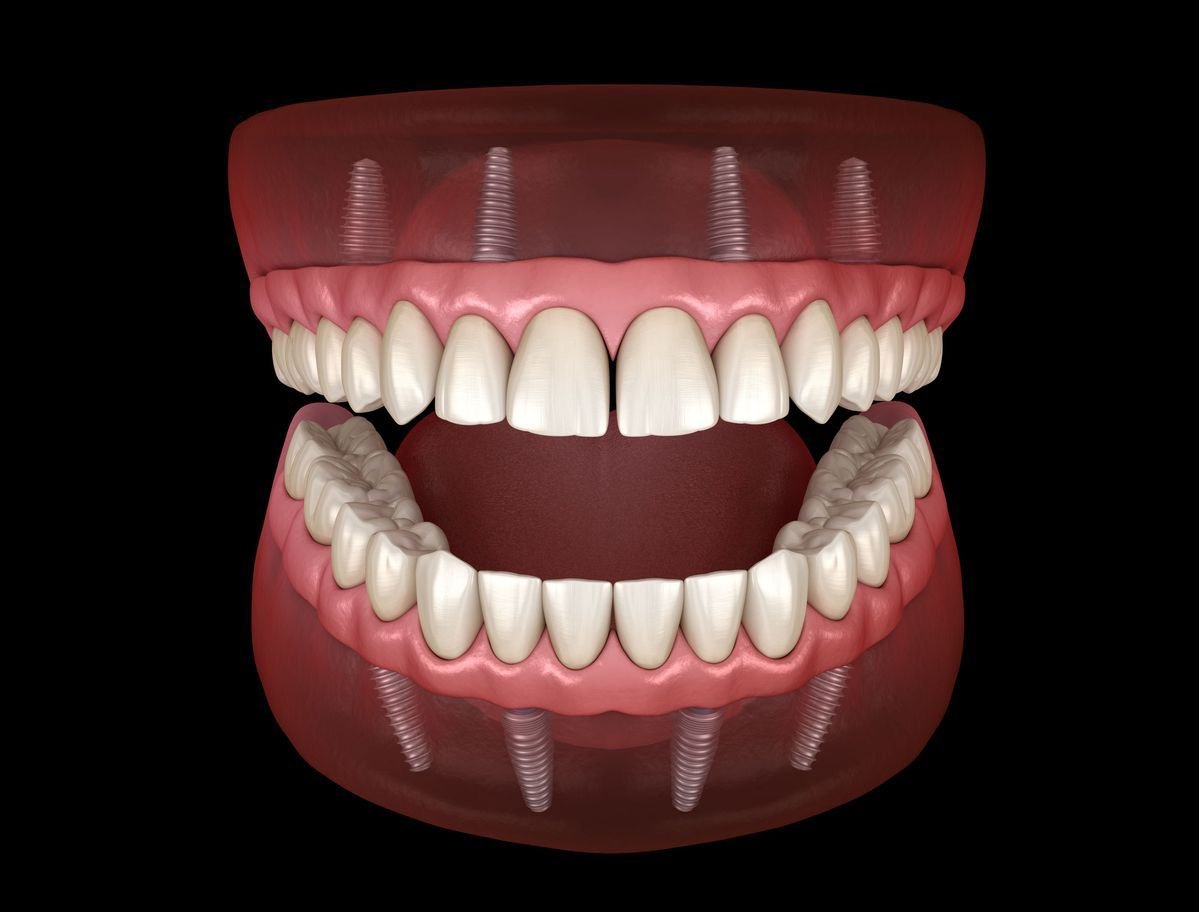

All-on-4 is an advanced implant treatment where four dental implants are placed in the jaw to support a full arch of fixed teeth (upper or lower jaw).

Two implants are placed vertically at the front, and two are placed at an angle at the back — allowing maximum stability even in cases of reduced bone volume.